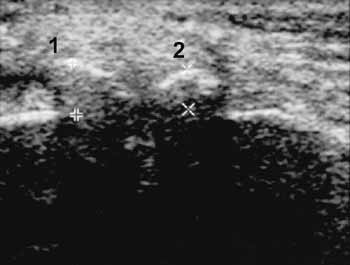

Рис. 10. Деформирующий остеоартроз, III стадия. Наружная поверхность

коленного сустава, сагиттальная проекция; выраженные краевые костные разрастания

бедренной (1+) и большеберцовой костей (2+).